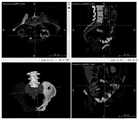

FIG. 7 is a schematic illustration of a pelvic bone image in an embodiment;

FIG. 8 is a schematic illustration of a target medical object in one embodiment;

In one embodiment, shown in combination with fig. 7 and 8, wherein fig. 7 is a schematic diagram of a pelvic bone image in one embodiment, and fig. 8 is a schematic diagram of a target medical object in one embodiment, in which the medical object image to be processed is a pelvic bone image, the initial medical object region is a pelvic bone region, and the target medical object is a sacrum and/or ilium; after the target medical object is obtained by segmenting the initial medical object region through the target medical object recognition model, the method comprises the following steps: acquiring a symmetry axis of a pelvic region, and performing mirror image operation according to the sacrum and/or the ilium of the symmetry axis; pelvic repair is performed from the sacrum and/or ilium after the mirroring procedure.